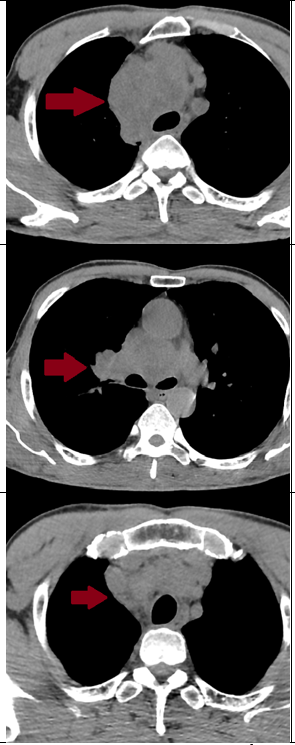

Hình 4. So sánh hình ảnh chụp cắt lớp vi tính lồng ngực của bệnh nhân trước và sau 3 tháng điều trị (các khối trung thất giảm kích thước đáng kể, kích thước lớn nhất 15x25mm – mũi tên màu vàng

=> Bệnh nhân đạt đáp ứng tốt với điều trị: khối u thu nhỏ kích thước đáng kể, lâm sàng được cải thiện rõ rệt. Trong quá trình điều trị, bệnh nhân có xuất hiện một số tác dụng phụ như: mệt mỏi, chán ăn, ngủ kém sau truyền hóa chất 2-3 ngày, ngoài ra chưa phát hiện các tác dụng phụ khác.

Đánh giá theo tiêu chuẩn RECIST 1.1, bệnh đáp ứng một phần (PR – Partial Responce). Hiện tại, bệnh nhân tiếp tục được điều trị phác đồ Atezolizumab - Etoposide - Carboplatin đủ 6 chu kỳ.